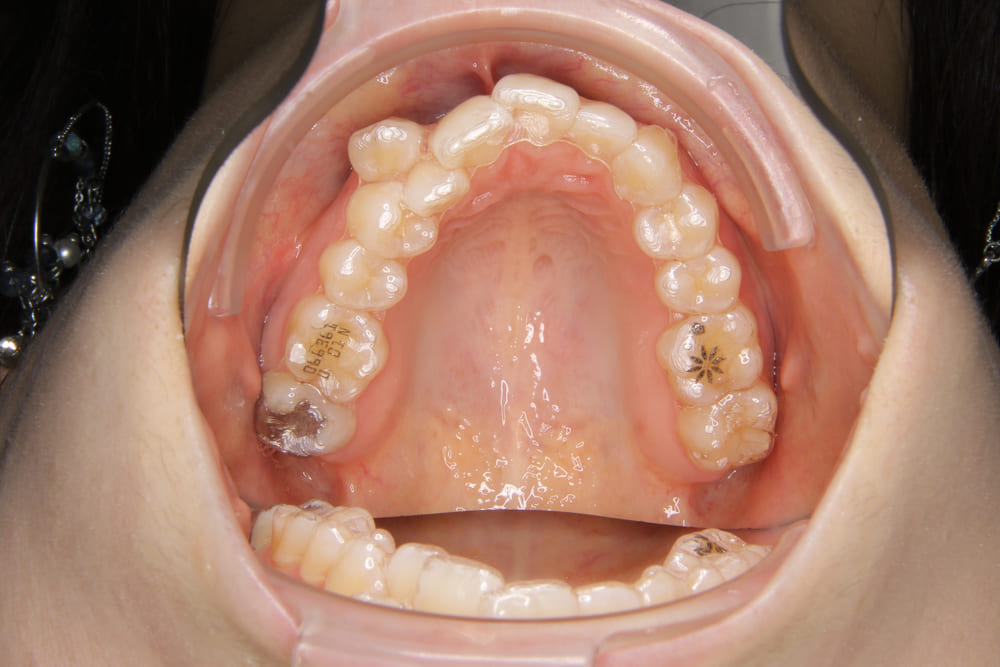

2精密検査

レントゲン撮影、口腔内写真・顔貌の写真撮影、口腔内スキャナー(iTeroなど)による精密な歯型採得など、治療計画の立案に必要なデータを収集します。

Q.虫歯や歯周病などの病気があっても、矯正できますか?

A. 最初の診断で虫歯や歯周病があった場合は、矯正を始める前にお口のトラブルを治療します。万が一、矯正中に虫歯ができてしまった場合は、矯正に影響が出ないように虫歯治療を行います。